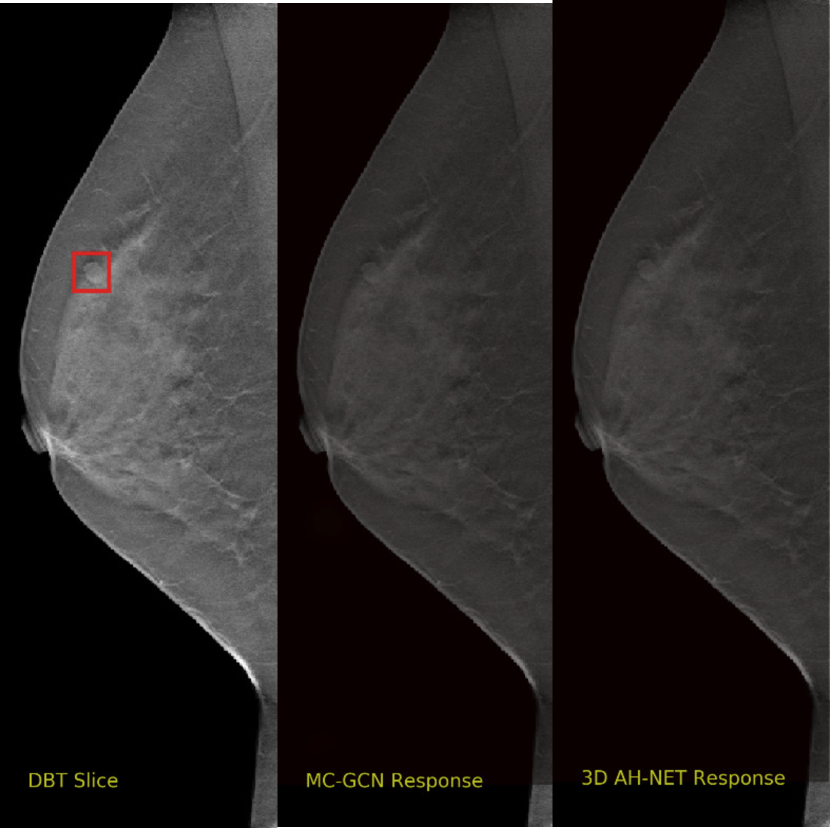

We selected some example slices from the DBT dataset to demonstrate the advantage of our proposed AH-Net for the Breast cancer screening. From Fig. 8 to Fig. 12, we show slices from five test DBT volumes that both the MC-GCN and the proposed 3D AH-Net could successfully detect the suspected breast lesion. The original DBT slice is shown on the left with the lesion annotated by our radiologist. Please note the original annotation is a 3D box. The figures in the middle and on the right are response maps from MC-GCN and 3D AH-Net overlaid on the original image, respectively. The detection locations obtained with non-maximal suppression are displayed with cross markers. As shown in the images, the proposed network can detect breast lesions varying in sizes and appearances. The confidence of the 3D AH-Net is usually higher than that of MC-GCN. From Fig. 13 to Fig. 17, we show five volumes that MC-GCN failed to detect the lesions since the lesions were not distinguishable from other breast tissues using the information within the slice. In contrast, 3D AH-Net was able to detect the lesions from such volumes using the 3D context between slices. As shown in Fig. 18 to Fig. 22, there are also volumes with lesions that both network failed to detect. Such lesions normally reside in the dense breast tissues. The boundary between these lesions and the normal breast tissues usually have low contrast. The networks sometimes also confuse them with other roundish structures in the breast such as lymph nodes or skin moles.

Refer to caption

Figure 13: Example DBT slice 6 with a lesion that can only be detected by 3D AH-Net. The lesion is highly blended within the dense breast tissues which makes it challenging for both the radiologists and the networks to detect through a single slice. In contrast, the lesion can be detected by considering the consistency of the structure across a few neighbouring slices.

Figure 14: Example DBT slice 7 with a lesion that can only be detected by 3D AH-Net. The lesion is highly blended within the dense breast tissues which makes it challenging for both the radiologists and the networks to detect through a single slice. In contrast, the lesion can be detected by considering the consistency of the structure across a few neighbouring slices.

Figure 15: Example DBT slice 8 with a lesion that can only be detected by 3D AH-Net. The lesion is small and hard to be distinguished from other breast tissues. The lesion can be detected by considering the consistency of the structure across a few neighbouring slices.